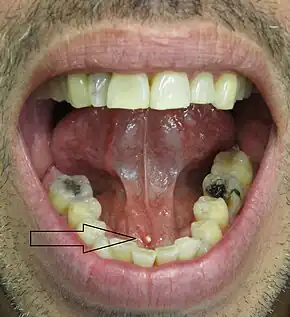

- Palpable hard lump, if the stone is located near the end of the duct.[6][7] If the stone is near the submandibular duct orifice, the lump may be felt under the tongue.

- Erythema (redness) of the floor of the mouth (infection).[7]

- Pus discharging from the duct (infection).[7]

Diagnosis is usually made by characteristic history and physical examination. Diagnosis can be confirmed by x-ray (80% of salivary gland calculi are visible on x-ray), by sialogram, or by ultrasound.

Ultrasound image of sialolithiasis- Stone resulting in inflammation and dilation of the duct[9]